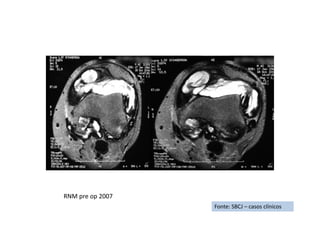

Sinovite vilonodular pigmentada difusa

• Resumo do caso: Recidiva de sinovite vilonodular pigmentada após ressecção